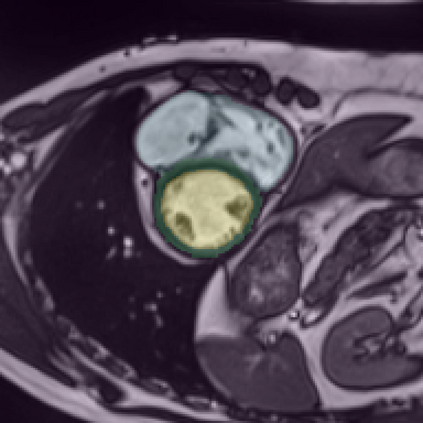

Supervised deep learning-based methods yield accurate results for medical image segmentation. However, they require large labeled datasets for this, and obtaining them is a laborious task that requires clinical expertise. Semi/self-supervised learning-based approaches address this limitation by exploiting unlabeled data along with limited annotated data. Recent self-supervised learning methods use contrastive loss to learn good global level representations from unlabeled images and achieve high performance in classification tasks on popular natural image datasets like ImageNet. In pixel-level prediction tasks such as segmentation, it is crucial to also learn good local level representations along with global representations to achieve better accuracy. However, the impact of the existing local contrastive loss-based methods remains limited for learning good local representations because similar and dissimilar local regions are defined based on random augmentations and spatial proximity; not based on the semantic label of local regions due to lack of large-scale expert annotations in the semi/self-supervised setting. In this paper, we propose a local contrastive loss to learn good pixel level features useful for segmentation by exploiting semantic label information obtained from pseudo-labels of unlabeled images alongside limited annotated images. In particular, we define the proposed loss to encourage similar representations for the pixels that have the same pseudo-label/ label while being dissimilar to the representation of pixels with different pseudo-label/label in the dataset. We perform pseudo-label based self-training and train the network by jointly optimizing the proposed contrastive loss on both labeled and unlabeled sets and segmentation loss on only the limited labeled set. We evaluated on three public cardiac and prostate datasets, and obtain high segmentation performance.